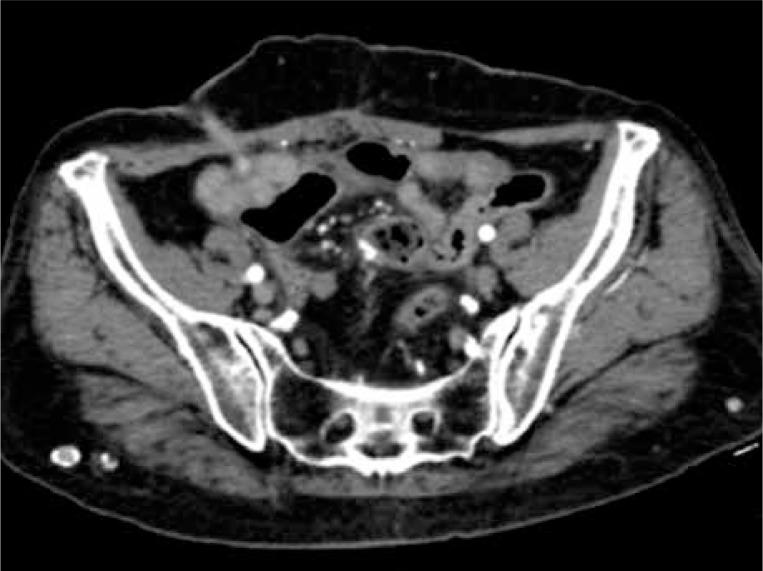

视频辅助肛瘘治疗(VAAFT)是2006年由梅内罗描述的一种用于治疗复杂性肛瘘的新型微创保括约肌技术。肠皮肤瘘是肠道与皮肤之间的异常通道。大多数病例继发于手术并发症,对外科医生来说,处理这种情况是一项真正的挑战。术后瘘占所有肠皮肤瘘的75 - 85%。本文的目的是设计一种微创技术来治疗肠皮肤瘘。我们将VAAFT的相同原理应用于其他情况,将瘘管的腔内视野与结肠镜检查相结合以确定内口。我们报告一例78岁女性患者,因盲肠和乙状结肠同步腺癌接受了全结肠切除术。术后病程并发肠皮肤瘘,采用保守措施治疗,随访期间复发。我们使用瘘管镜联合结肠镜进行了视频辅助瘘管治疗。一旦确定了瘘管,我们对瘘管进行了清理和破坏,应用了合成氰基丙烯酸酯,并通过腔内方法用夹子封闭了内口。患者5天后出院,无并发症。两个月后伤口完全愈合,无复发迹象。该手术代表了一种使用微创技术治疗肠皮肤瘘的替代方法,特别是对于那些无法接受大手术的特定患者。